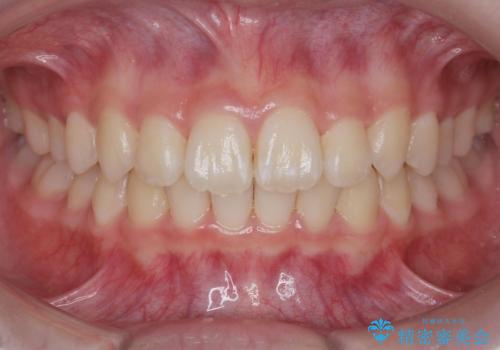

子供の出っ歯 生え代わりと成長期を利用して非抜歯で矯正

- 出っ歯を主訴に来院。

生え代わりを待ってから矯正を始めました。

特に右側のかみ合わせがずれていたため、上の奥歯を後ろに下げています。

下顎も前方に成長し、前歯のかみ合わせも同時に深かったのを浅くすることができました。